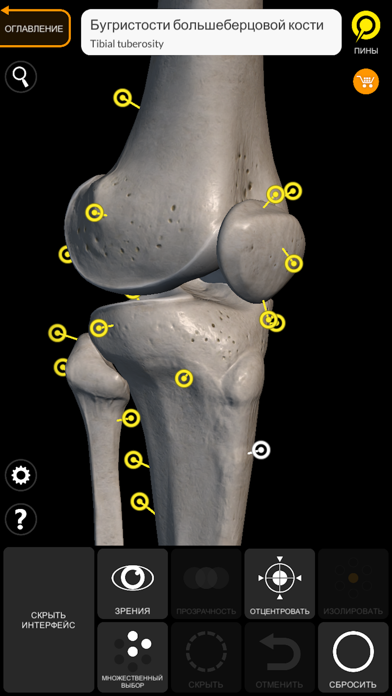

Скриншоты